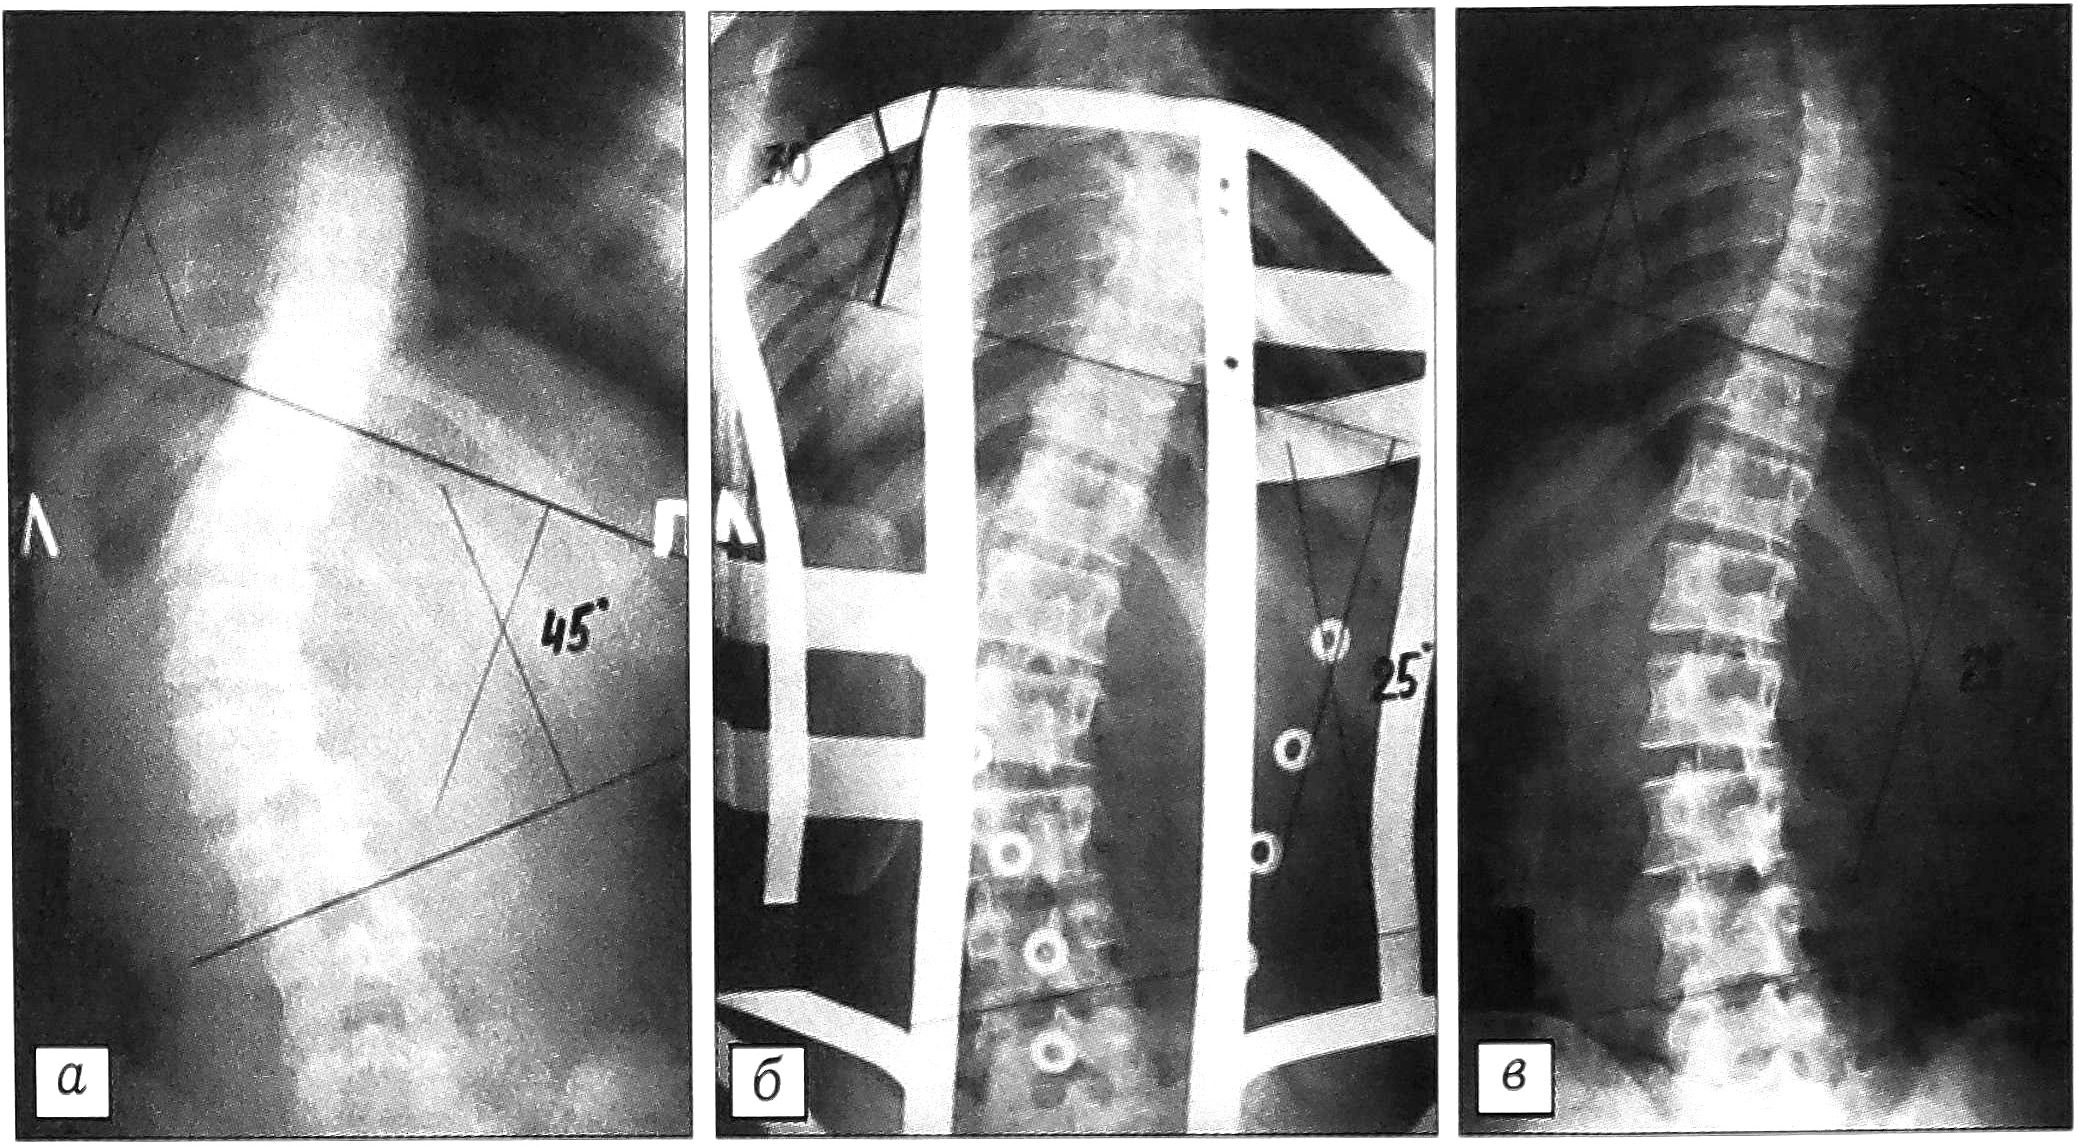

В качестве примера приводим рентгенограммы двух больных — с комбинированным сколиозом II степени (рис. 4) и III степени (рис. 5).

Рис. 4. Рентгенограммы больной В. 14 лет. Диагноз: комбинированный идиопатический сколиоз II степени. а — до лечения; б — в корсете; в — через 12 мес после начала реабилитационного лечения.

Рис. 5. Рентгенограммы больной К. 16 лет. Диагноз: комбинированный идиопатический сколиоз III степени. а — до лечения; б — в корсете; в — через 12 мес после начала реабилитационного лечения.